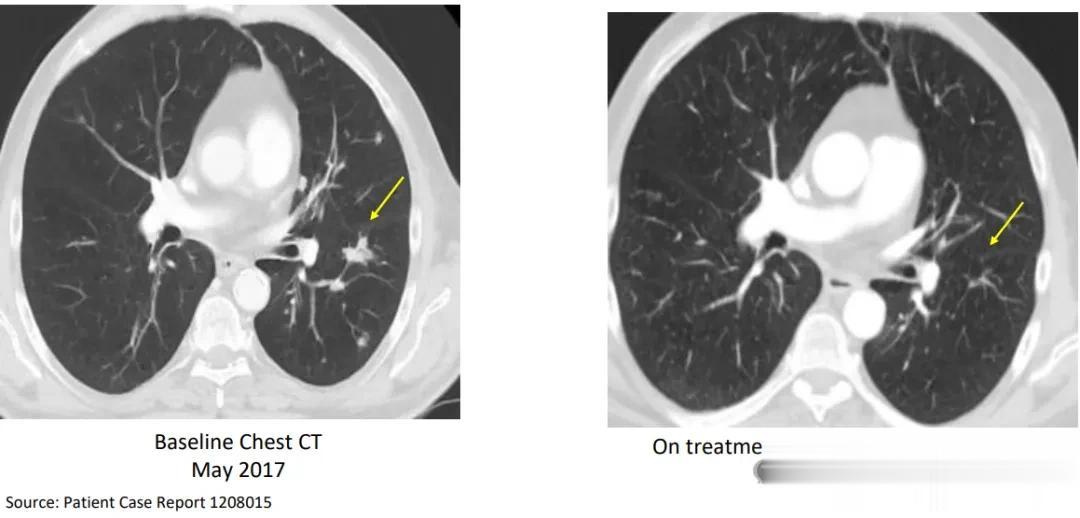

1名54岁的晚期肺癌患者在经过5次的新型肺癌疫苗注射后,肿瘤就迅速萎缩,靶病灶总和减少41%(直径从39mm降至23mm),截止报道时,生存期已经超过20.6个月,目前仍在随访中。

典型患者病例(部分缓解)